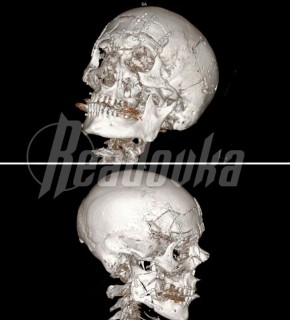

По версии следствия, 54-летний обвиняемый, являясь на момент совершения преступления лидером ОПГ в Самарской области, дал указание группе лиц за денежное вознаграждение совершить убийство начальника Тамбовского РОВД Валерия Джураева, ранее возглавлявшего подразделение по борьбе с организованной преступностью. Сотрудник правоохранительных органов был убит 13 апреля 2000 года на выходе из здания областной больницы на улице Московской в Тамбове.